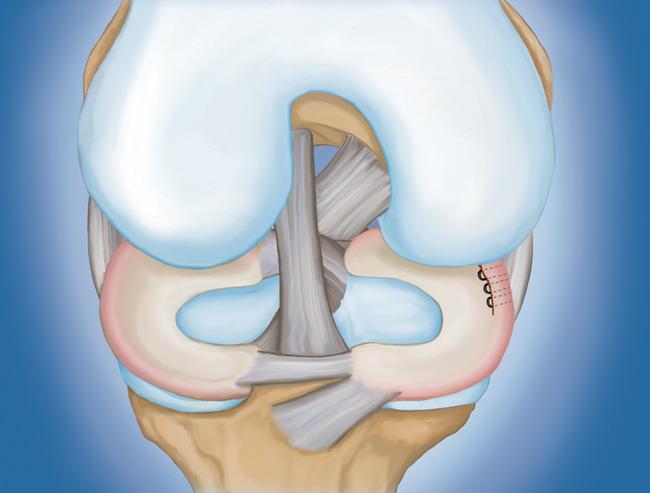

- 半月板修復。 一些半月板撕裂可以通過將撕裂的碎片縫合(縫合)在一起來修復。撕裂能否成功修復取決于撕裂的類型,以及受傷半月板的整體狀況。因為半月板必須一起愈合,修復的恢復時間比半月板切除術長。

初步愈合完成后,您的醫生將進行康復鍛煉。定期鍛煉以恢復膝關節的靈活性和力量是必要的。您將從鍛煉開始,以改善您的運動范圍。力量訓練將逐漸添加到您的康復計劃中。

在許多情況下,康復可以在家中進行,但您的醫生可能會建議您與物理治療師一起工作。半月板修復的康復時間約為3至6個月。半月板切除術需要更少的愈合時間——大約3到6周。